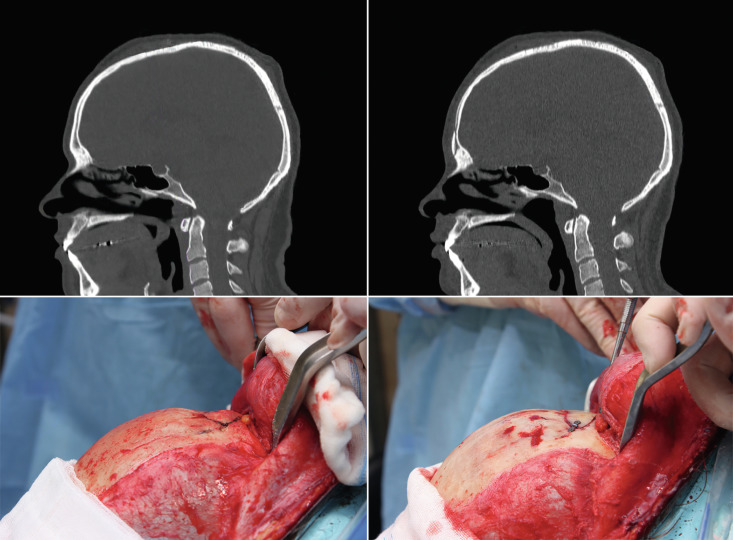

Forehead Reconstruction

This is one of the basic procedures in facial feminization. It completely modifies the frontonasoorbital region and softens and feminizes the patient’s expression. The surgical plan is devised to open the frontonasal angle, retroposition the anterior wall of the frontal sinus, open the orbital areas, soften the entire forehead surface, and reposition the eyebrows above the new supraorbital ridge, while always maintaining the anatomical integrity of the entire area ( Figs. 8.5 and 8.6 ). The sequence in Fig. 8.7 provides a step-by-step description of the reconstruction technique proposed by our team. Despite the fact that other authors defend different techniques (isolated burring, the use of filling materials), in our experience, the proposed reconstruction technique offers satisfactory and safe results regardless of the anatomy of the frontal region ( Fig. 8.8 ).

Finally, it is important to discuss the best access (approach route) to reach the frontal bone region: modified coronal approach (anterior or posterior) or hairline approach. In our opinion, this access should be based on the characteristics of the patient’s hairline and its implantation (the distance from the nasal root to the beginning of the hairline).